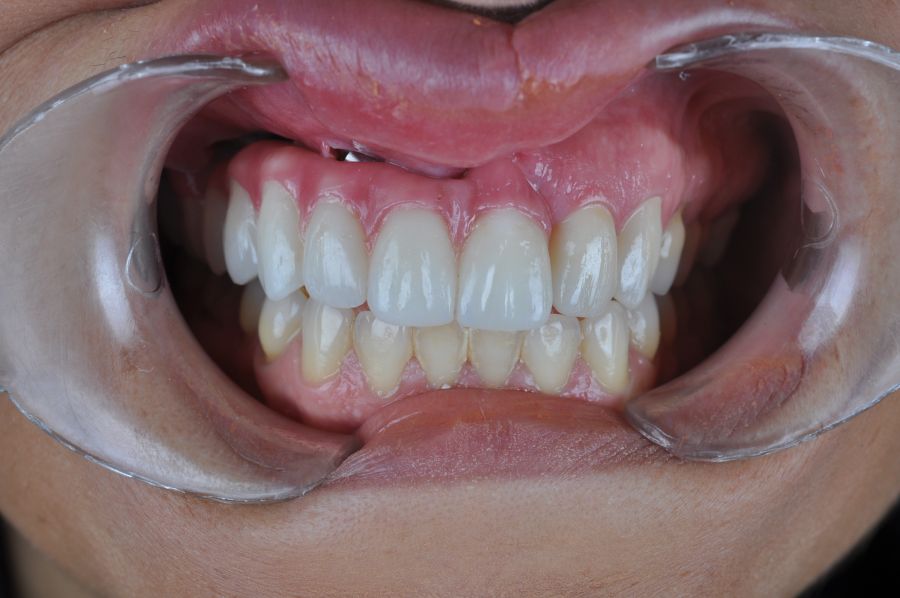

Para la fabricación de las estructuras, se eligió el óxido de zirconio monolítico como material restaurador sobre interfases metálicas en el puente implantosoportado, y coronas de óxido de zirconio monolítico en los dientes tallados previamente (1.7, 1.6, 2.2 y 2.3). Se tomaron impresiones de cubeta abierta con silicona de adición pesada y fluida (Zhermack Elite HD, Gmbh). Se realizó una prueba de pasividad analógica y el resto del proceso se confeccionó de manera digital, por lo que se hicieron pruebas estéticas de dientes impresas en 3D sobre interfases metálicas, para hacer todos los ajustes de función y estética previos al fresado del zirconio monolítico (Figuras 11, 12 y 13).

El día de la colocación de las estructuras, se arenó el interior de las coronas dentosoportadas con óxido de aluminio de 50 m y fueron cementadas con cemento de resina Multilink Ò. El puente implantosoportado se atornilló al torque indicado (20Nw) (Figuras 14, 15, 16 y 17).